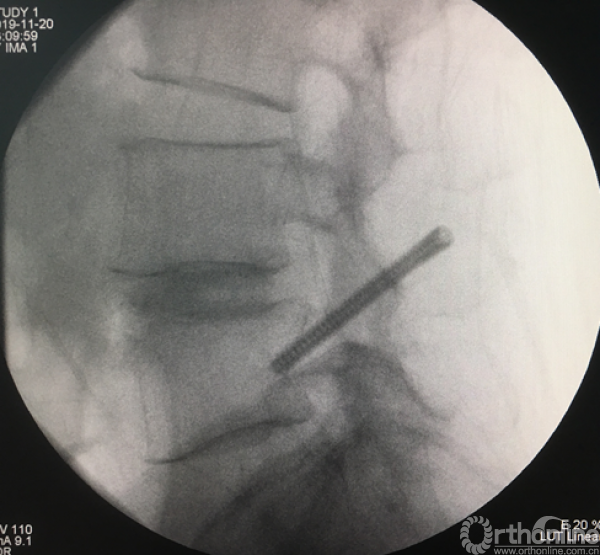

植入EndoPIN,运用扩张管、克氏针以及动力电钻等工具

植入经皮椎弓根钉并加压